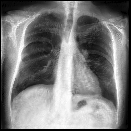

Disease-aware image editing by means of generative adversarial networks (GANs) constitutes a promising avenue for advancing the use of AI in the healthcare sector. Here, we present a proof of concept of this idea. While GAN-based techniques have been successful in generating and manipulating natural images, their application to the medical domain, however, is still in its infancy. Working with the CheXpert data set, we show that StyleGAN can be trained to generate realistic chest X-rays. Inspired by the Cyclic Reverse Generator (CRG) framework, we train an encoder that allows for faithfully inverting the generator on synthetic X-rays and provides organ-level reconstructions of real ones. Employing a guided manipulation of latent codes, we confer the medical condition of cardiomegaly (increased heart size) onto real X-rays from healthy patients. This work was presented in the Medical Imaging meets Neurips Workshop 2020, which was held as part of the 34th Conference on Neural Information Processing Systems (NeurIPS 2020) in Vancouver, Canada